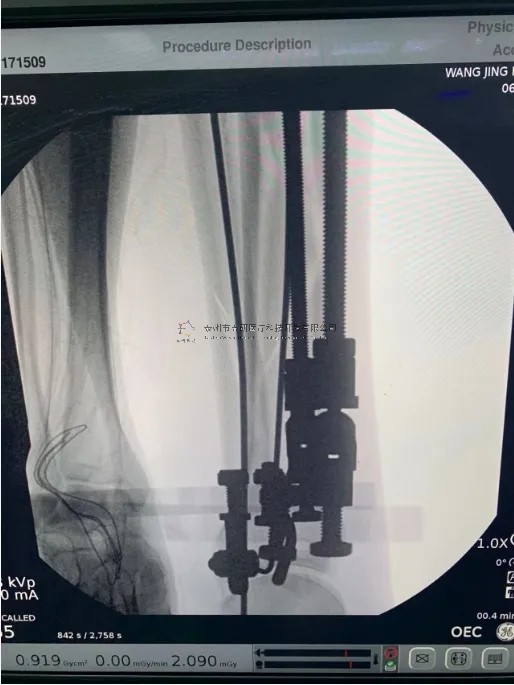

2月份,我們在中國中醫(yī)科學(xué)院望京醫(yī)院就有多臺關(guān)于外固定支架的手術(shù),以下介紹一則不開刀CO接骨治療小腿骨折典型病例:

【患者情況】左脛腓骨近端骨折

【影像圖片】

【手術(shù)資料】